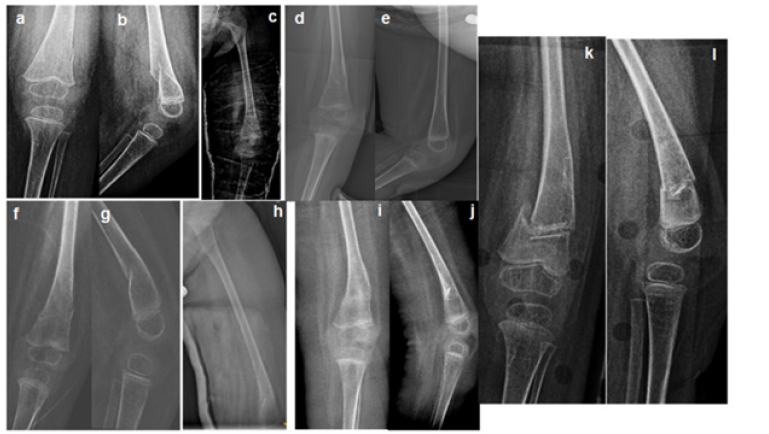

Figure 1: Serial plain X-rays of the sustained metaphyseal femur fracture and the subsequets. Initial fracture lines in antero-posterior a) and lateral b) proyections, incomplete consolidation after 4 weeks by cast immobilization c) and fracture consolidation after 6 weeks, antero-posterior d) and lateral e) proyections respectively. Second fracture, that is to be the first refracture in antero-posterior f) and lateral g) proyections. Control after 4 weeks h) and anteroposterior d) and lateral e) proyections of fracture consolidation at 6 weeks. Third and last metaphyseal femur fracture, that is to be the second refracture in antero-posterior k) and lateral l) proyections.

A 2-year-old girl, with history of thoracolumbar MMC and, subsequently, flaccid paraplegia, thoracolumbar scolisis, coxa valga and hip instability, developed swelling in left knee without pain, fever, worsening of general condition or discomfort with the palpation of the femur and knee joint, which, however, crackled with the mobilization. The patient had not suffered any obvious trauma. Plain antero-posterior and lateral X-ray showed a nondisplaced, well aligned fracture of the distal femoral metaphysis (Figure 1a & 1b), so conservative treatment was decided by immobilization with an inguinopedic cast. After 4 weeks, a new X-ray showed incomplete callus formation (Figure 1c), so the immobilization was extended two more weeks, after which, appropriate osteosynthesis was achieved, although the bones exhibited cortical thinning and loss of bone trabeculation in the metaphysis, suggestive of osteoporosis. After 8 weeks, load over both lower limbs was resumed, with the help of a standing orthosis to guarantee a safe and adequate joints control during the loading. In a blood test, vitamin D deficiency (25- hydroxyvitamin D=21ng/mL) was found, accompanied with an increased urine calcium excretion, so calcium and vitamin D supplements were prescribed (Figure 1d & 1e).

Two months after the restarting of the standing, once again, swelling in the same left knee was discovered. Plain X-ray confirmed a new metaphyseal femur fracture just over the previous fracture callus (Figure 1f & 1g). As also this time the fracture line was neat and the bone fragments were not displaced, conservative approach with inguinopedic cast was chosen. A z score -2 was detected in the femur dual X-ray absorptiometry (DXA). To improve the bone modelling bisphosphonates were proposed, but due to an intercurrent episode of urinary tract infection, their administration was temporarily postponed. The cast was removed after 6 weeks (Figure 1i & 1j) and the loading through a standing orthosis recommenced after 9 weeks. Vitamin D and calcium supplements were maintained to reach a level of 25- hydroxyvitamin D up to 30ng/mL.

Almost a year after the first refracture, a new finding of mild swelling coexisting with left knee crackled with mobilizations made us suspect a second refracture of the former callus, that was confirmed in the X-ray (Figure 1k & 1l).